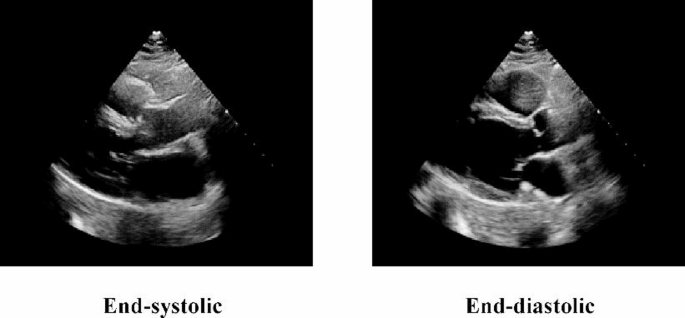

The EchoNet-Dynamic dataset consists of 10,030 echocardiography videos in the apical-4-chamber (A4C) view10. These videos were acquired at Stanford University Hospital between 2016 and 2018 using a variety of ultrasound machines. The dataset is labeled by human experts with values for Ejection Fraction (EF), End-Systolic Volume (ESV), and End-Diastolic Volume (EDV). A separate annotation file specifies the exact frame numbers corresponding to end-systole and end-diastole for each video. Crucially for our segmentation task, this file also provides the ground truth coordinates (X1, Y1, X2, Y2) that trace the border of the left ventricle in these keyframes. All videos have been cropped to a 112 × 112 pixel resolution to remove information outside the imaging sector. The details of the EchoNet-Dynamic dataset are summarized in Table 2, and Fig. 2 shows a sample image of this dataset.